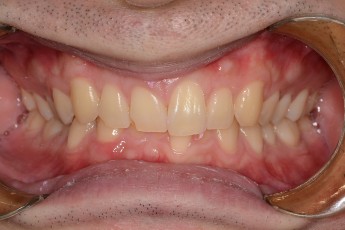

BEFORE & AFTER

- 덧니교정